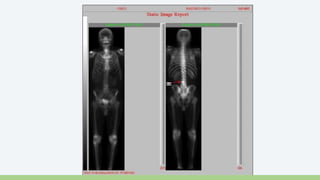

Gammagrafía Ósea

• Útil para detección de Metástasis Oseas

• Indicada en Pacientes con

• PSA +10

• Gleason +7

• Dolor Óseo

• Tecnecio 99

Gammagrafía Ósea •Útil para detección de Metástasis Oseas • Indicada en Pacientes con • PSA +10 • Gleason +7 • Dolor Óseo • Tecnecio 99